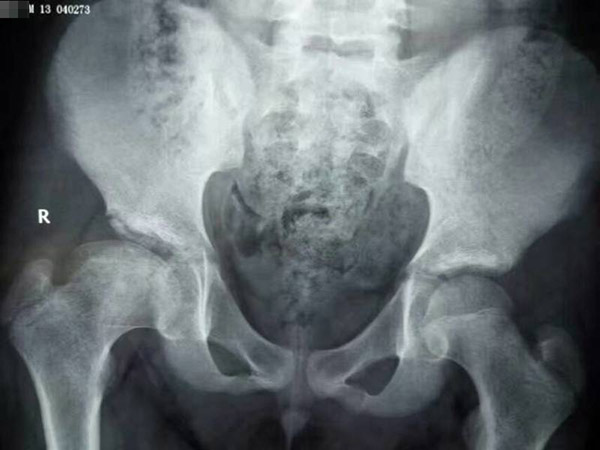

治疗后

在朋友的介绍下,亮亮的父母来到郑州中医骨伤病医院,经过不到两年的治疗,今年14岁的亮亮完已经全康复了。医生告诉他的父母,不用担心什么后遗症,现在亮亮好了完全是因为你们家长的这份心,如果不是当初的坚持,也不会有今天的结果。